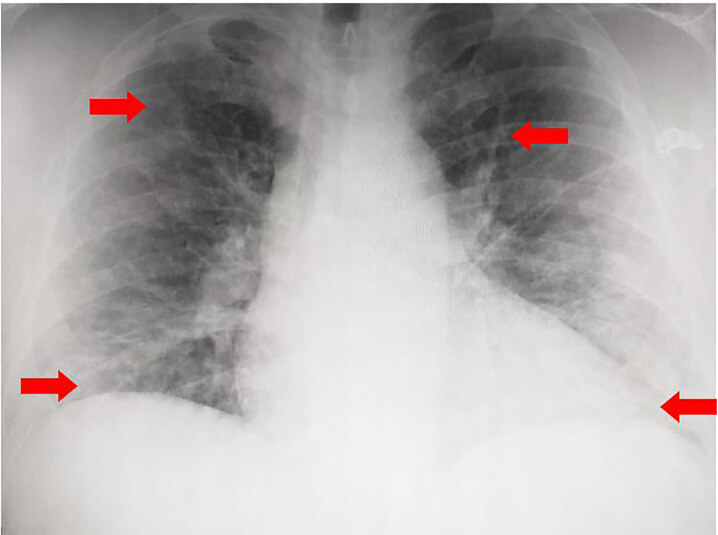

НемедицинаFigure 1. Первичная рентгенограмма грудной клетки демонстрирует умеренную отек легочных сосудов с легким, неясным двусторонним поражением дыхательных путей, вероятно, вторичным по отношению к альвеолярному отеку или аспирации (стрелки).